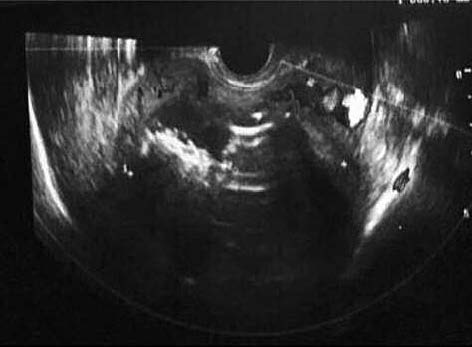

Пациентке Е. проводилась многокомпонентная антибактериальная, инфузионная и симптоматическая терапия в течение 10 дней, которая позволила добиться улучшения состояния женщины (удовлетворительного состояния), нормализации температуры тела, нормализации лабораторных показателей, однако кровянистые выделения из половых путей продолжались. Консилиумом врачей было принято решение о проведении эмболизации маточных артерий (ЭМА). Произведена селективная катетеризация с последующей ангиографией левого (рис. 2, а) и правого (рис. 3, а) передних стволов внутренних подвздошных артерий.

Рис. 2. Процедура ЭМА. Ангиограмма левой маточной артерии до введения (а) и после введения эмболизата (б).

Через катетеры, установленные последовательно в левой и правой маточной артерии, введены сферы эмболизата Contour (Boston Scientific): 1 флакон 500–700 мкр дробно. На контрольных ангиограммах: афферентные артерии к образованиям матки окклюзированы. Длительный стаз контрастированной крови в стволах левой (рис. 2, б) и правой (рис. 3, б) маточных артерий. Катетер и интрадьюсер удалены. Наложена асептическая давящая повязка. Нежелательных реакций и осложнений интраоперационно не наблюдалось.